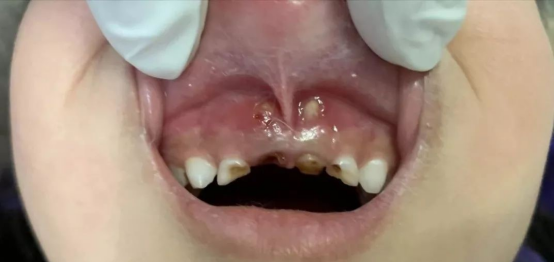

“虫牙”又称“龋齿”,虽然宝宝的乳牙最终会被恒牙替换,但孩子换牙是有时间顺序的,从6岁到12岁左右都是换牙期。而恒牙是“潜伏”在乳牙下面慢慢发育的。如果乳牙坏了,恒牙胚周围会肿胀、流脓甚至鼓包,这样不仅会引起恒牙表面的牙釉质发育不全,牙齿少了这层最坚硬“外壳”的保护,寿命也会缩短;而且还会导致牙槽骨缺如,宝宝的恒牙就会长得歪歪扭扭。

当孩子乳牙有了龋齿,如果家长不及时为孩子治疗“生病”的乳牙,等到孩子自己喊疼了,吃东西不舒服了,或者牙龈长脓包了,这时多数虫牙已经发展到了牙髓炎或者根尖炎的阶段,这种情况下的治疗就需去除乳牙的牙髓,不仅增加了孩子痛苦,还可能影响恒牙的萌出和生长。如果乳牙龋齿早期发现,只需要经过简单的充填,就会达到很好的临床治疗效果。所以建议粑粑麻麻们如果发现孩子患有乳牙龋齿,要及早带其到医院进行检查和治疗,不要延误最好的治疗时机,以免给孩子带来更多的痛苦。